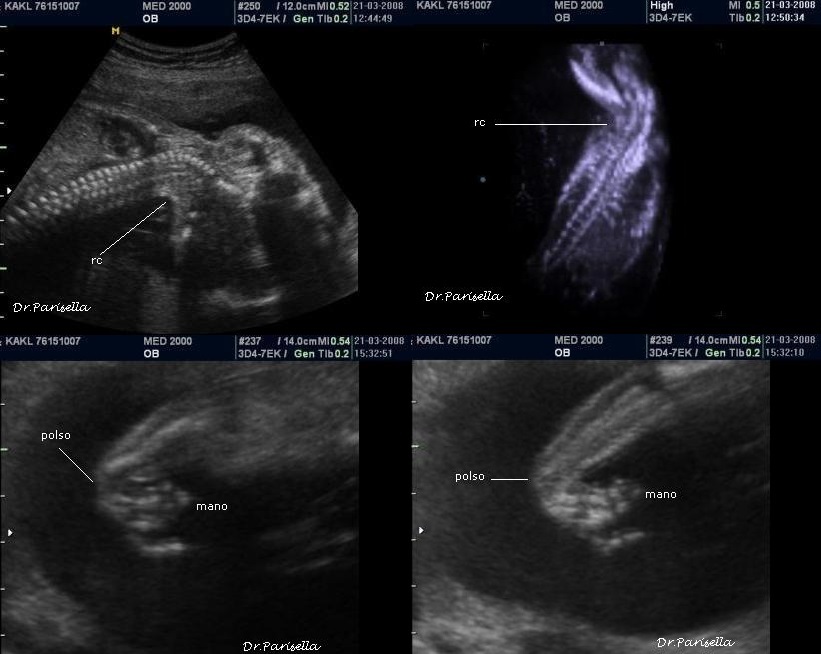

La diagnosi prenatale si basa su:

1) assenza di movimenti attivi fetali;

2) contratture articolari;